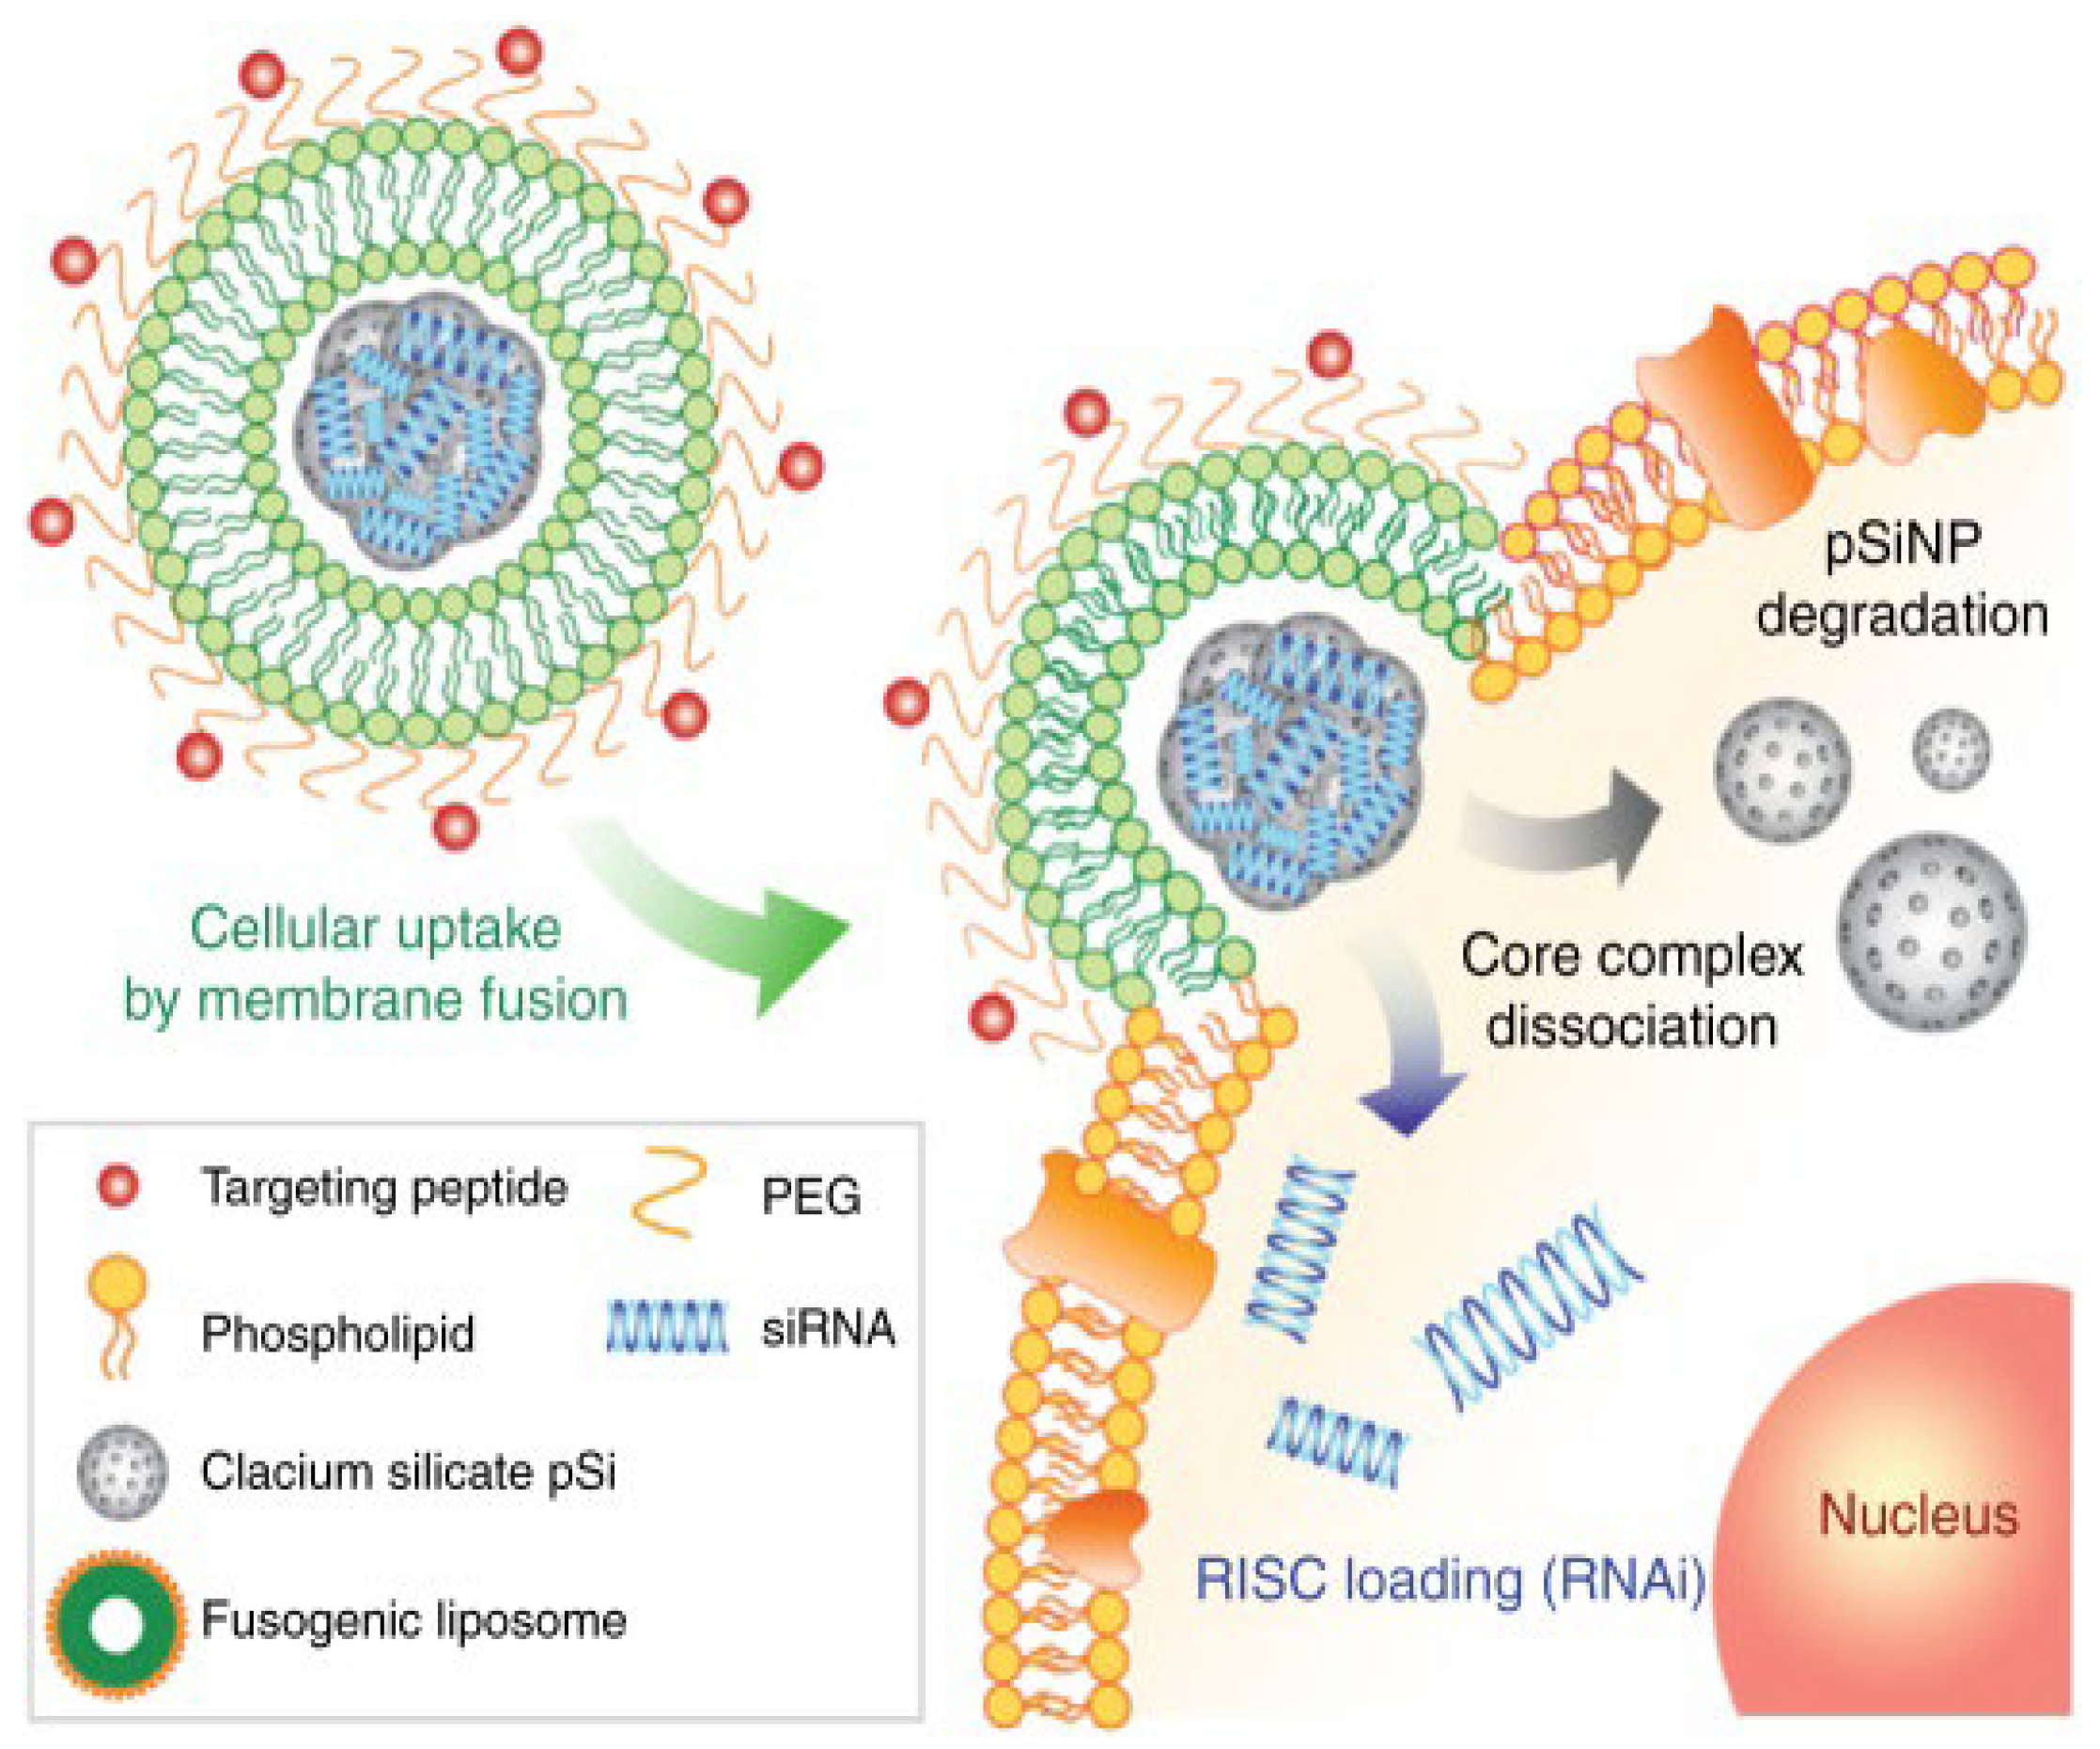

4.2. Liposomes

- Scriboni, A.B.; Couto, V.M.; Ribeiro, L.N.d.M.; Freires, I.A.; Groppo, F.C.; de Paula, E.; Franz-Montan, M.; Cogo-Müller, K. Fusogenic Liposomes Increase the Antimicrobial Activity of Vancomycin Against Staphylococcus aureus Biofilm. Front. Pharmacol. 2019, 10, 1401. [Google Scholar] [CrossRef] [PubMed]

- Kim, B.; Pang, H.-B.; Kang, J.; Park, J.-H.; Ruoslahti, E.; Sailor, M.J. Immunogene Therapy with Fusogenic Nanoparticles Modulates Macrophage Response to Staphylococcus aureus. Nat. Commun. 2018, 9, 1969. [Google Scholar] [CrossRef] [PubMed]